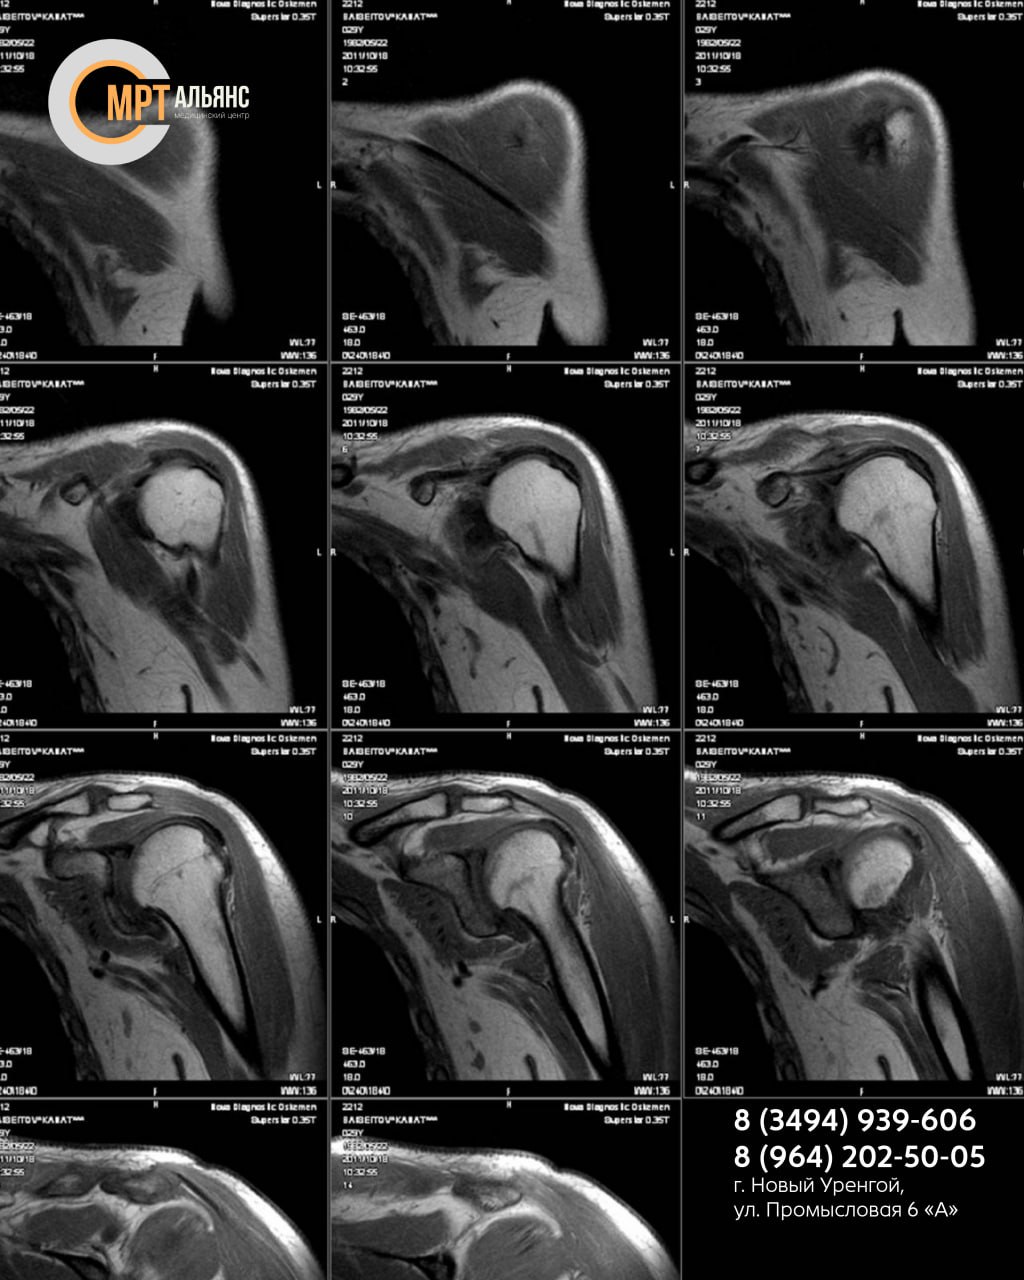

МР-сканирование послойно визуализирует ткани плеча с точностью до 1 мм, оценивая состояние:

• мягких тканей

• сосудов

• костей

• нервных корешков

Выявляем:

• воспаления, опухоли, трещины хрящей

• сдавливание сосудов, травмы, патологии суставов (артрит, тендинит, бурсит и др.)

• скрытые повреждения после ушибов, подвывихов

МР-исследование проводится при подозрении на патологии плеча: инфекционные, аутоиммунные, травматические, воспалительные, некротические, нейропатические и другие